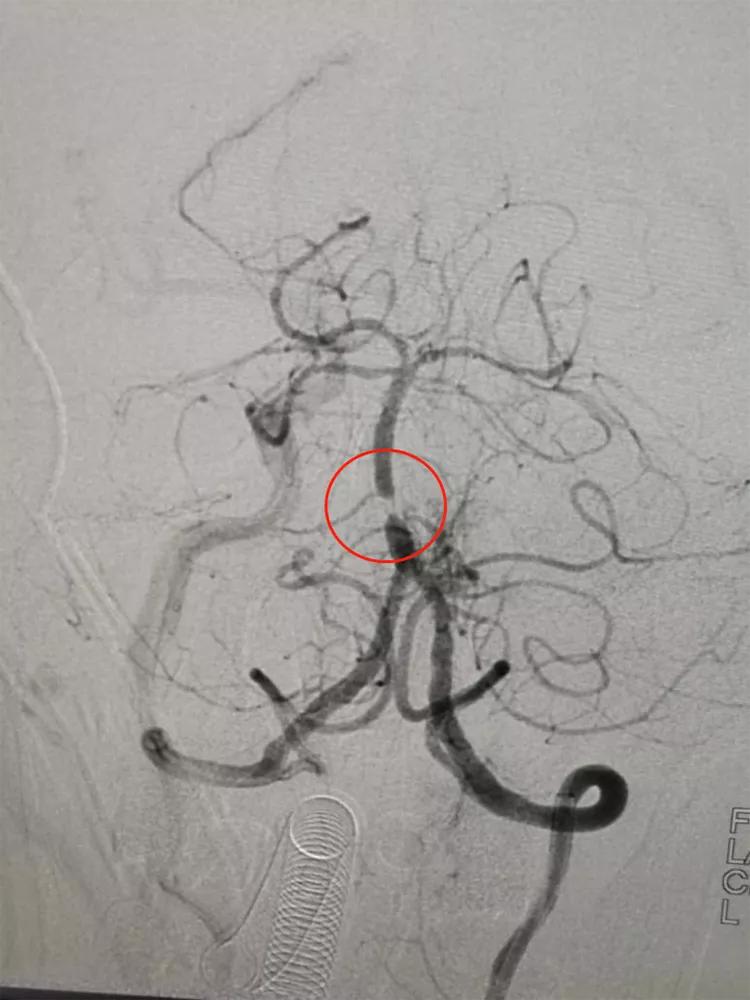

支架成形术前,基底动脉下段重度狭窄

支架成形术后,基底动脉狭窄解除